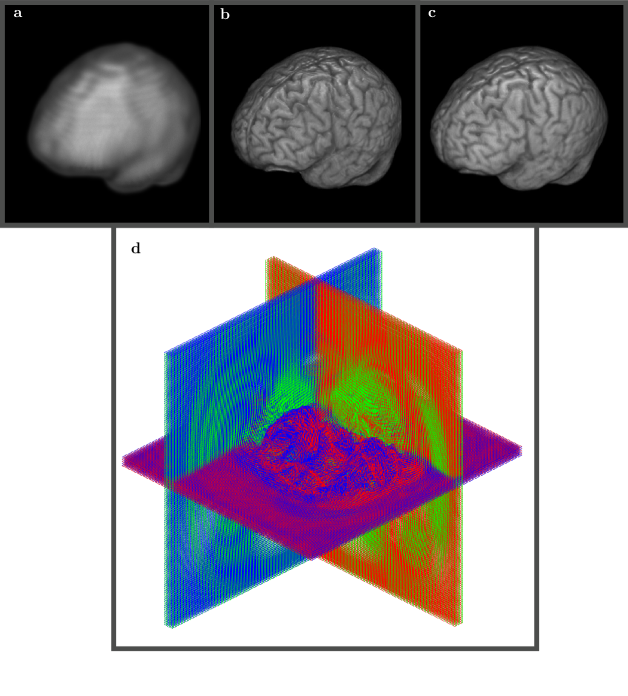

Figure 6 shows side by side comparison for 3D views of rs-FMRI (a), T1 (b) and rs-FMRI mapped to T1 (c) volumes. The processing was carried through 30 energy embedded shells and required about 5 minutes of waiting time from the start to the finish, with a subset of the final grid shown in (d). The work is currently underway to include flexible mapping grids directly to our rs-FMRI mode detection approach [79, 80].

Refer to caption

Fig 6: 3D view of low resolution (64x64x30) rs-FMRI volume (a) vs T1 high resolution (290x262x262) anatomical volume (b). SWD preconditioned rs-FMRI volume after registration to high resolution T1 template (c). The final mapping grid used 30 shells (d) and took about 5 minutes on 12 cores Intel® CoreTM i7-4930K CPU 3.40GHz. The same color scheme is used for the displacement field with blue corresponding to the anterior-posterior grid lines, green to the dorsal-ventral grid lines, and red to the right-left lateral grid lines.